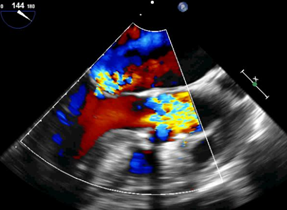

球扩释放主动脉瓣瓣中瓣

黄焕雷主任带领具有丰富经验的心脏麻醉医师、体外循环师、超声心动图医师、手术室、心外重症监护室、心脏导管室多学科团队,联合心内科专家谢年谨主任,为蔡先生实施小切口下、介入途径的主动脉瓣“瓣中瓣”、二尖瓣“环中瓣”的同期植入手术:黄主任首先在患者左前胸做一小切口,暴露患者的心尖,在跳动的心脏上“绣”上荷包作为介入导管、瓣膜的植入“门户”;随后,黄焕雷主任在超声心动图、放射透视的引导下,将一钢针在患者心尖“扎”入患者心脏内,为之后的瓣膜植入作为引导,具体来说就是将预先选择适合患者大小的生物瓣膜折叠、压缩入细长的输送管道内,好比将瓣膜这一“弹头”安放在输送导管这颗精准制导的“火箭”上,而黄主任的双手则控制这一精准发射和制导,再将瓣膜输送到主动脉合适的位置后释放,新的主动脉瓣便牢固地“卡”在了原有的主动脉瓣架内。经过透视和超声心动图评估,主动脉瓣位置合适,开放、闭合功能良好。随后,黄主任通过这一根钢针和输送导管,利用类似的方式,调整“火箭”的发射轨道,在原有二尖瓣人工瓣环内植入预先选择好大小的二尖瓣生物瓣膜,经过影像学方式评估,新植入的二尖瓣生物瓣工作良好。